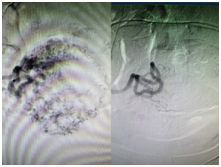

经皮穿刺插管选择性子宫动脉造影,明胶海绵颗粒栓塞剂注入双侧子宫动脉,造影证实达到预期栓塞效果,术后24小时在B超引导下行吸宫术,术中出血约10ml。术后认真护理及治疗,无并发症发生。